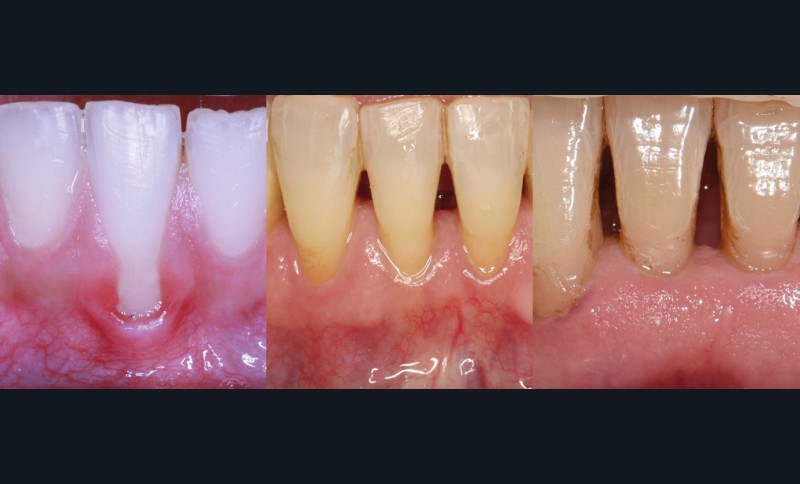

La récession RT1 est une récession sans perte d’attache interproximale et où la JAC est cliniquement non détectable en zone interproximale, le recouvrement complet est possible. Lorsque la perte d’attache interproximale est inférieure ou égale à la perte d’attache vestibulaire, on parlera de récessions RT2, le recouvrement ne sera que partiel. La récession RT3 est une récession où la perte d’attache interproximale est supérieure à la perte d’attache vestibulaire, dans ce cas-là le recouvrement est impossible. Il est important aussi de savoir identifier et distinguer la récession gingivale de l’éruption passive incomplète qui est une anomalie de développement de l’éruption dentaire (fig. 1).

La greffe épithélio-conjonctive (GEC) [7, 8] consiste au remplacement du tissu parodontal existant par un greffon épithélio-conjonctif dont l’indication principale est l’augmentation en hauteur et en épaisseur du tissu kératinisé (fig. 2). Elle peut aussi être utilisée dans le recouvrement radiculaire (avec des résultats en termes de recouvrement inférieurs à ceux des techniques de greffe de conjonctif enfouie), l’aménagement des crêtes édentées, l’aménagement péri-implantaires [9, 10] (fig. 3), ou en association avec un traitement ortho-parodontal [11]. Le principal défaut de cette technique est son aspect inesthétique ; elle sera donc réservée à des zones non visibles comme les incisives mandibulaires ou les zones postérieures.